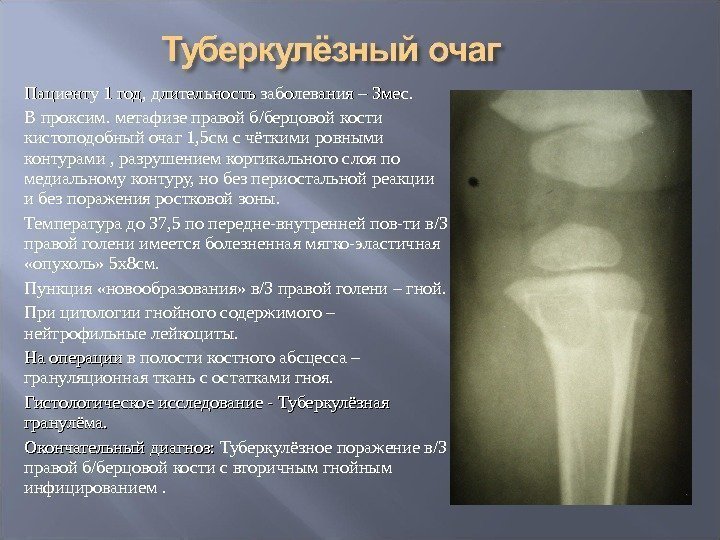

Медицинские аспекты заболеваний: рентгенологическая картина туберкулеза костей

Раздел: Снимки-откровения